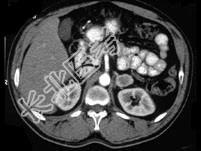

- 多项选择题女,34岁, 无意中发现血压升高4 个月就诊,行CT检查, 如图所示,下列说法正确的是 ( )

A、CT示左侧肾上腺区可见一等密度块影,边界清楚

B、增强扫描,该病灶周边明显强化,中心处强化不明显

C、考虑为左肾上腺腺瘤

D、考虑为左肾上腺嗜铬细胞瘤

E、考虑为左肾上腺转移瘤